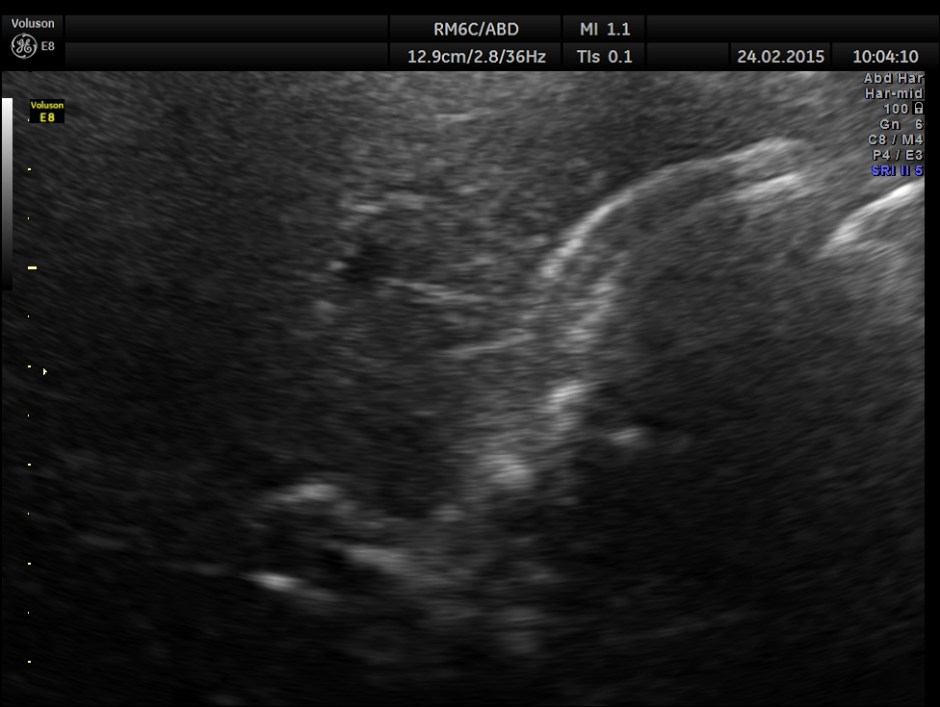

Completely collapsed and shrunk gall bladder in spite of over night fasting.